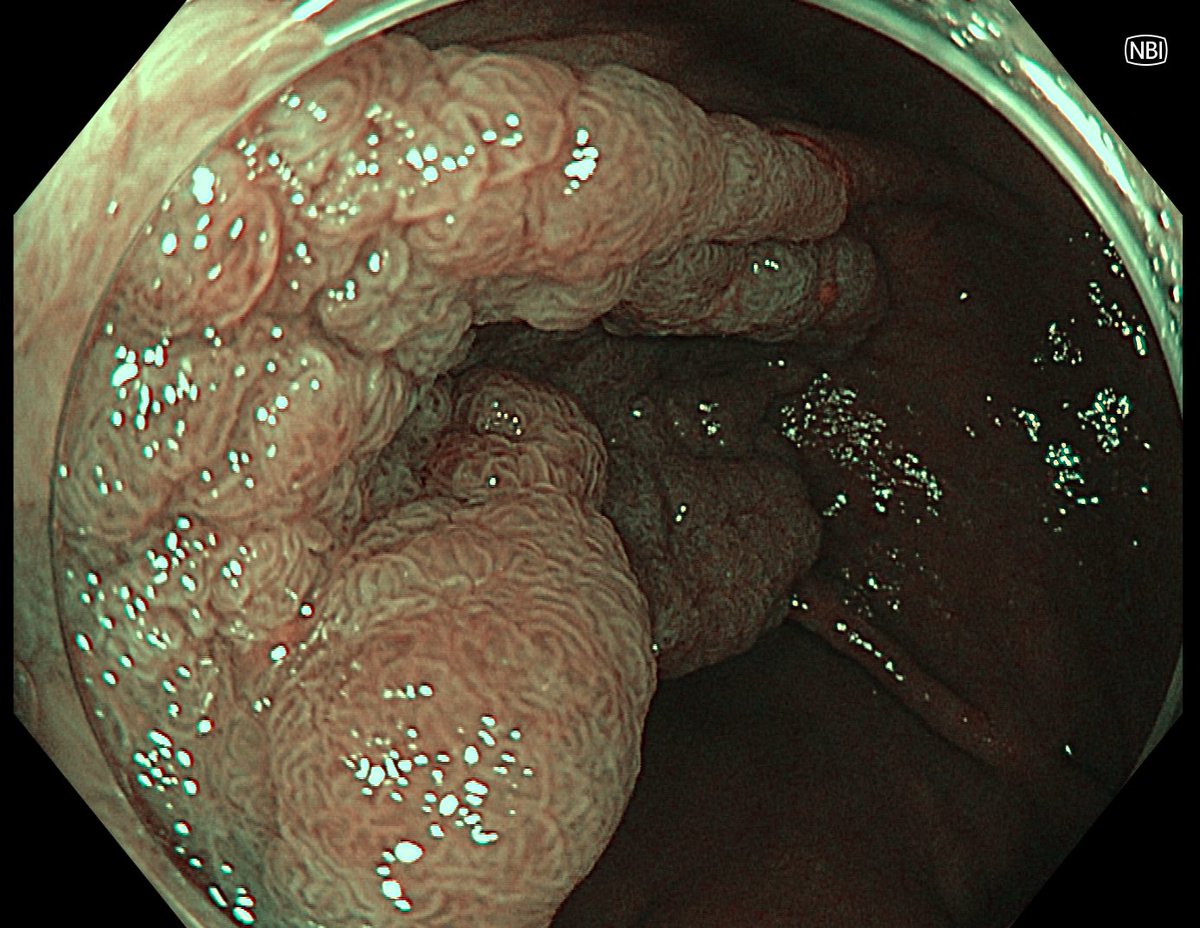

This lesion was diagnosed in the distal sigmoid colon? What do you do next?